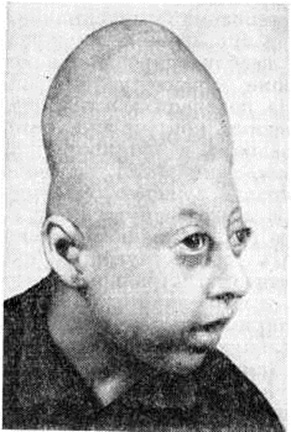

КраниостенозКраниостеноз (craniostenosis; греческий kranion череп + stenosis сужение) — особый вид патологического формообразования черепа, характеризующийся преждевременным синостозом отдельных или всех черепных швов, деформацией черепа, нарушениями структуры его костей, проявляющийся расстройствами зрения и различными симптомами недостаточности функций головного мозга. Краниостеноз может сочетаться с другими пороками развития (синдактилия, мозговая грыжа, заячья губа, волчья пасть, незаращение артериального протока, аномалии развития трахеи и бронхов и так далее). Краниостеноз встречается у 0,005—0,02% новорожденных. Описаны наследственные формы Краниостеноз Этиология и патогенез. Причины преждевременного заращения швов черепа не установлены. Их связывают с различными наследственными и внутриутробными заболеваниями. Патогенез преждевременного заращения швов и всю наблюдаемую при Краниостеноз неврологический симптоматику многие авторы объясняют первичными патологический изменениями в самом черепе и возникающим при этом несоответствии между объёмом внутричерепной полости и объёмом увеличивающегося в размере мозга. Вместе с тем высказывается обоснованное мнение, что раннее заращение черепных швов является только одним из признаков сложной врождённой патологии, в частности первичной патологии в развитии сосудистой системы головы. Изучение особенностей ангиоархитектоники и гемодинамики головы у больных Краниостеноз выявило аномалии вне и внутричерепных артерий и вен, а также выраженные в различной степени нарушения мозгового кровообращения. Эти нарушения выявляются в двух формах — в развитии венозного застоя с последующим нарастанием повышения внутричерепного давления и в развитии ишемического поражения мозга вследствие врождённых патологический изменений в магистральных артериях головы (смотри полный свод знаний Внутричерепное давление). В пользу сосудистой теории патогенеза Краниостеноз говорят экспериментальные данные, согласно которым у 2—4-дневных кроликов изменения кровообращения головы приводят к преждевременному заращению черепных швов. Клиническая картина. Существует множество классификаций Краниостеноз Однако большинство из них не удовлетворяет клиницистов либо неполнотой, либо громоздкостью, либо неточностью классификационных критериев. Клинико-морфологически различают следующие виды Краниостеноз (рисунок 1): 1) оксицефалия (смотри полный свод знаний Башенный череп) 2) скафоцефалия (ладьевидный череп); 3) плагиоцефалия (косой череп); 4) уступообразный череп (батроцефалия); плоский череп (платицефалия); треугольный череп (тригоноцефалия); 7) узкий череп (лептоцефалия); 8) черепно-лицевой дизостоз (смотри полный свод знаний); 9) акроцефалосиндактилия (смотри полный свод знаний Апера синдром). Каждая из этих форм Краниостеноз может быть как компенсированной, так и декомпенсированной. Длительное время считалось, что механизмы компенсации включаются только в связи с повышением внутричерепного давления. Сторонники сосудистой теории патогенеза Краниостеноз считают, что организм компенсирует имеющиеся сосудистые изменения и декомпенсация может развиваться или по типу «венозной энцефалопатии» или ишемии мозга. Клинически компенсированная форма Краниостеноз проявляется только изменением формы головы. Незначительные явления декомпенсации могут проявляться периодическими головными болями. При выраженной декомпенсации, помимо приступообразного характера головных болей, наблюдаются тошнота, рвота, застойные изменения на глазном дне с переходом в атрофию зрительных нервов или развивается их первичная атрофия, снижается зрение. Появляются признаки поражения и других черепно-мозговых нервов, изменяются физиологический рефлексы, нередко возникают эпилептические припадки. Изменения интеллекта встречаются относительно редко. Диагноз, как правило, не представляет особых затруднений. Характерный внешний вид больного с необычной формой черепа (рисунок 2) и данные рентгенологическое обследования позволяют установить диагноз без дополнительных исследований. Рентгенологические исследование черепа при Краниостеноз направлено в первую очередь на выявление признаков преждевременного заращения швов и деформаций черепа. На ранних стадиях развития Краниостеноз обнаруживают лишь сужение одного или нескольких швов, чаще всего сагиттального и венечного, и умеренный остеосклероз костных краёв шва, иногда на относительно небольшом протяжении. |

Рис 2. | ||